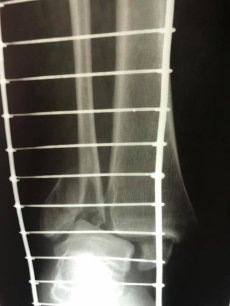

Завдяки вчасному зверненні та професіоналізму лікаря-ортопеда-травматолога, жінку вдалося врятувати. Волинянка з необережності впала на власному городі. В ургентному порядку жінку доставили в КНП «НЦМЛ». Після огляду лікар встановив діагноз: відламковий перелом кісточок гомілки з вивихом стопи.